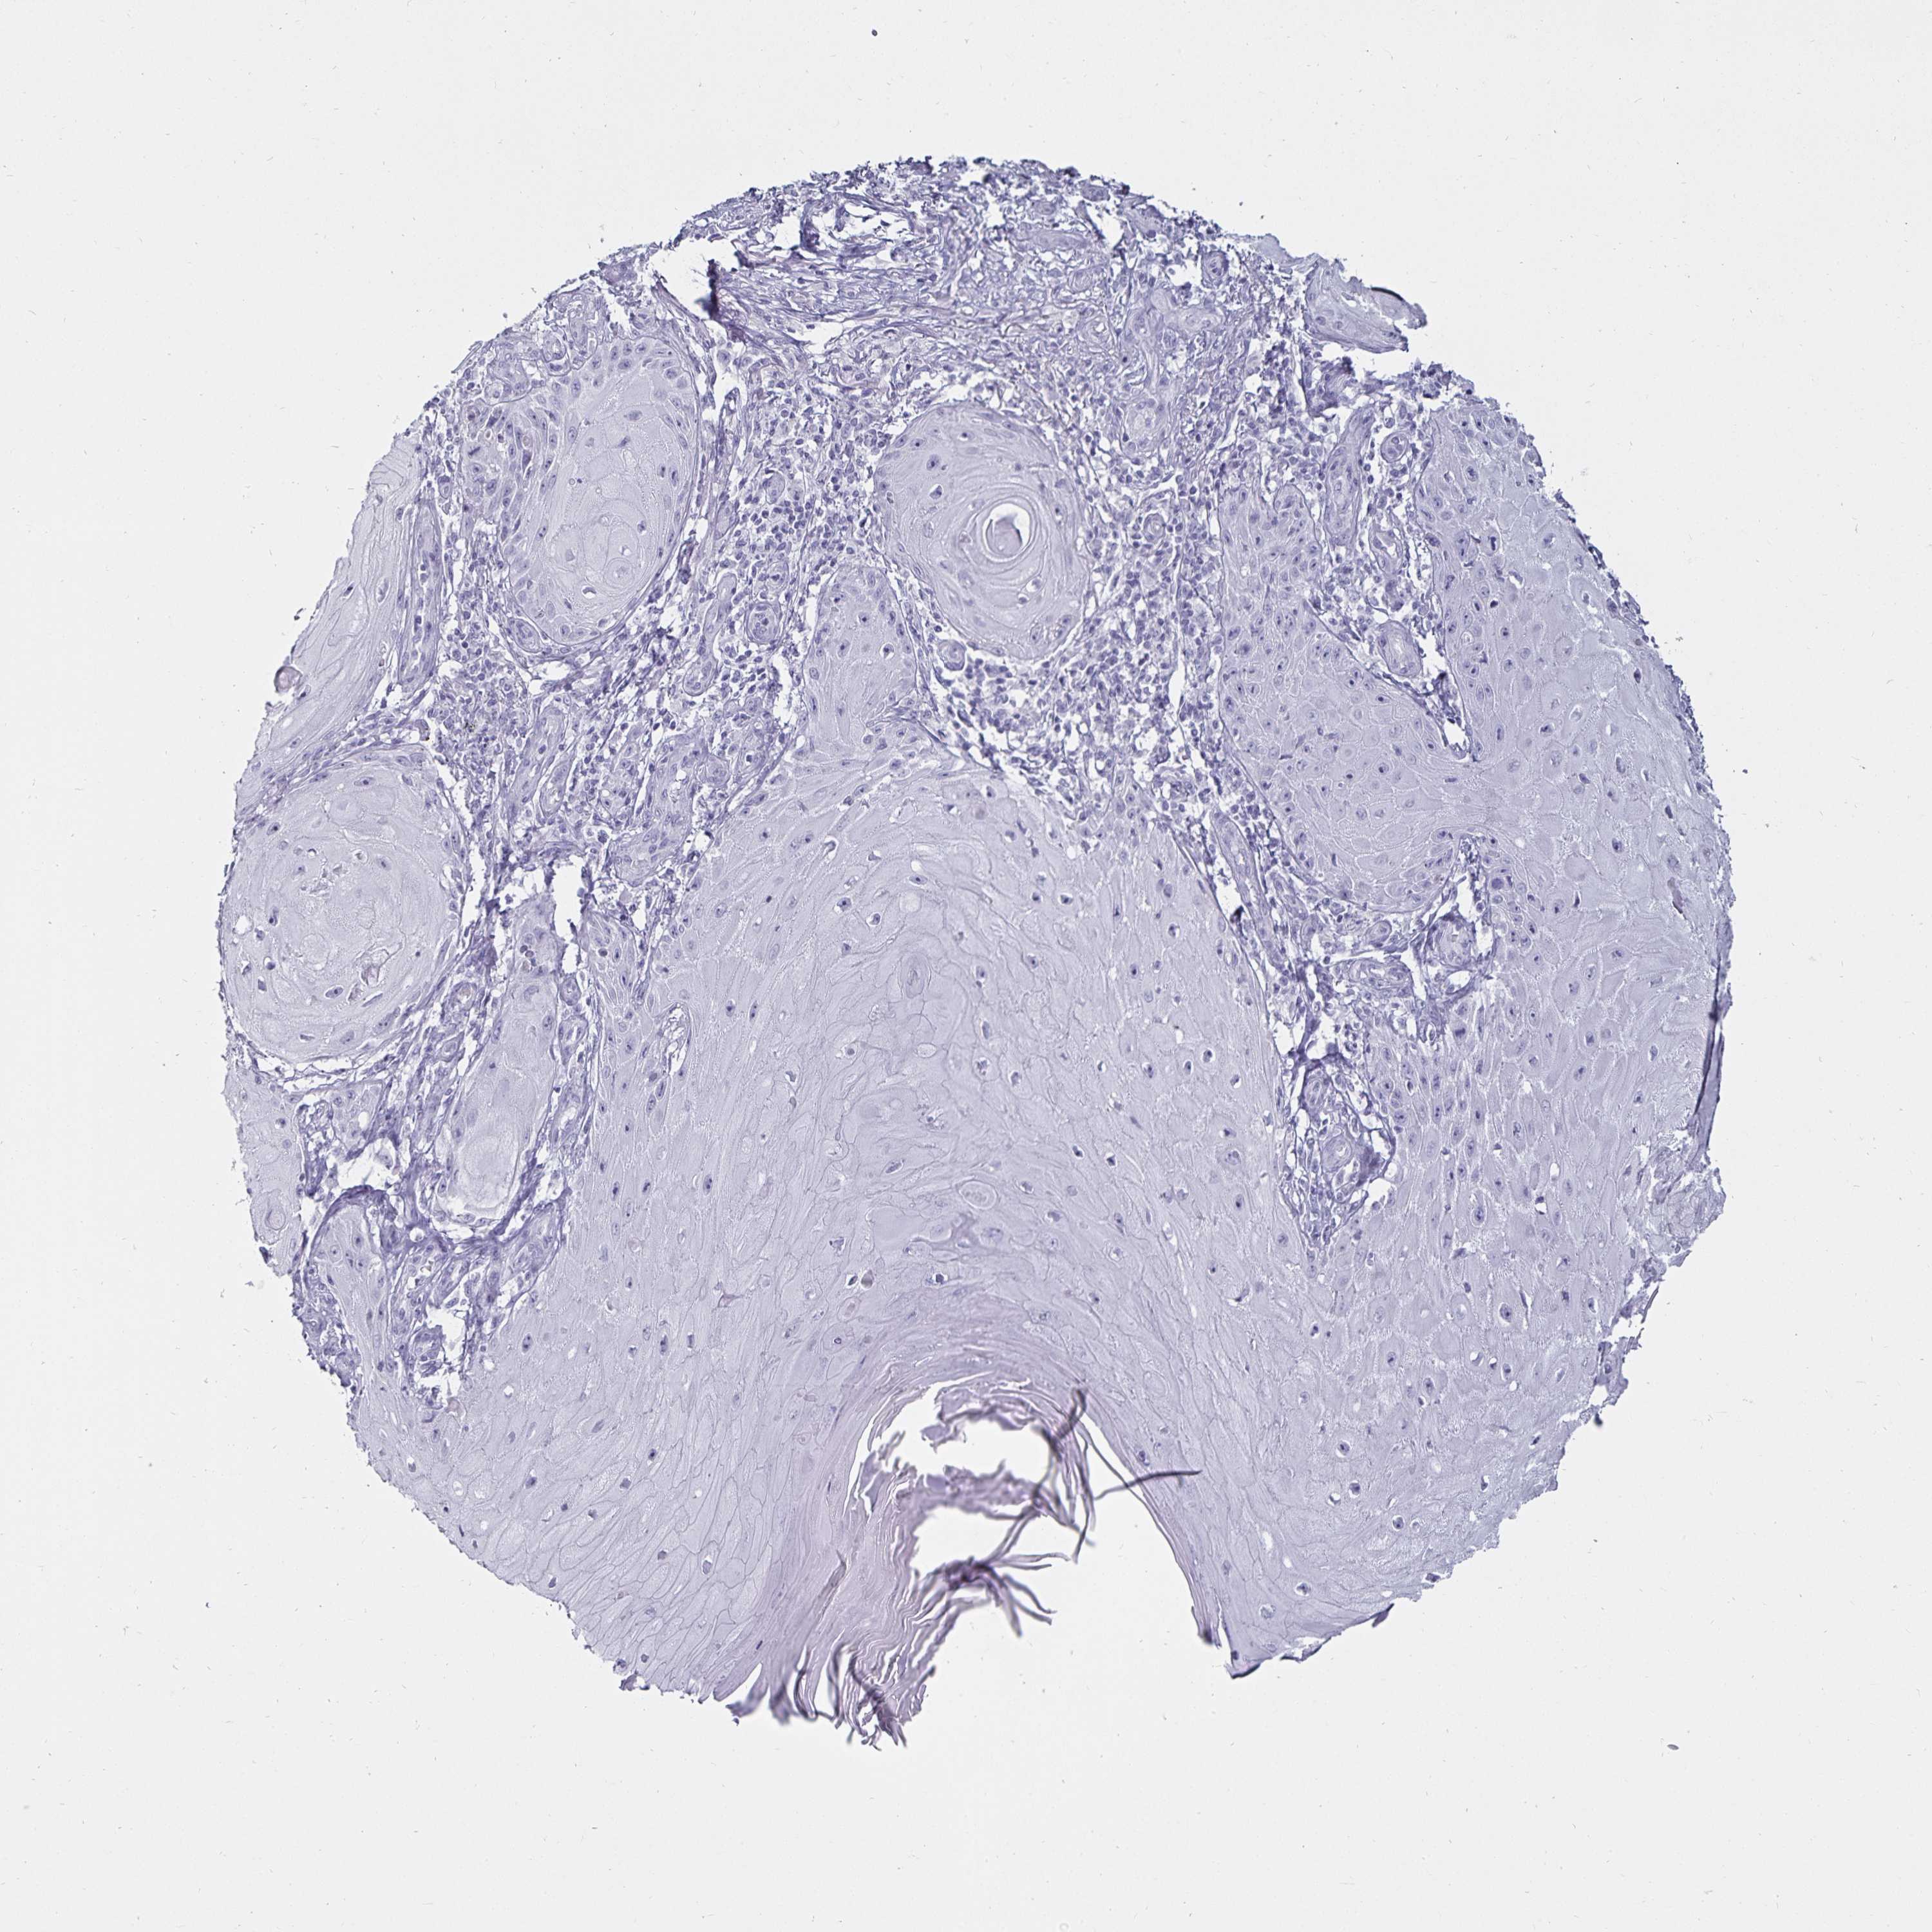

CANCER SKIN CANCER Show tissue menu

Basal cell and squamous cell cancer

SKIN CANCER - Protein expressioni

A mouse-over function shows sample information and annotation data. Click on an image to view it in a full screen mode. Samples can be filtered based on level of antibody staining by selecting one or several of the following categories: high, medium, low and not detected. The assay and annotation is described here.

Each image is clickable and will lead to virtual microscopy that enables deeper exploration of all samples and also displays staining intensity scores, fraction scores and subcellular localization as well as patient and tissue information for each sample.

Antibody HPA019462

Staining

High

Medium

Low

Not detected

Intensity

Strong

Moderate

Weak

Negative

Quantity

>75%

75%-25%

<25%

None

Location

Nuclear

Cytoplasmic/membranous

Cytoplasmic/membranous,nuclear

Basal cell carcinoma

Squamous cell carcinoma, NOS